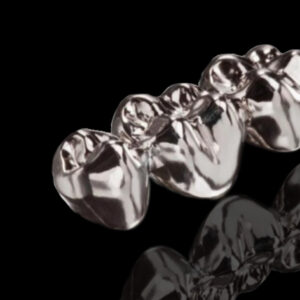

A digital denture is a modern dental prosthesis created using advanced digital technology, including 3D imaging, CAD/CAM (computer-aided design and manufacturing) and 3D printing. Digital dentures offer improved accuracy, comfort, and aesthetics compared to traditional dentures. They also reduce the number of visits required and the overall treatment time.